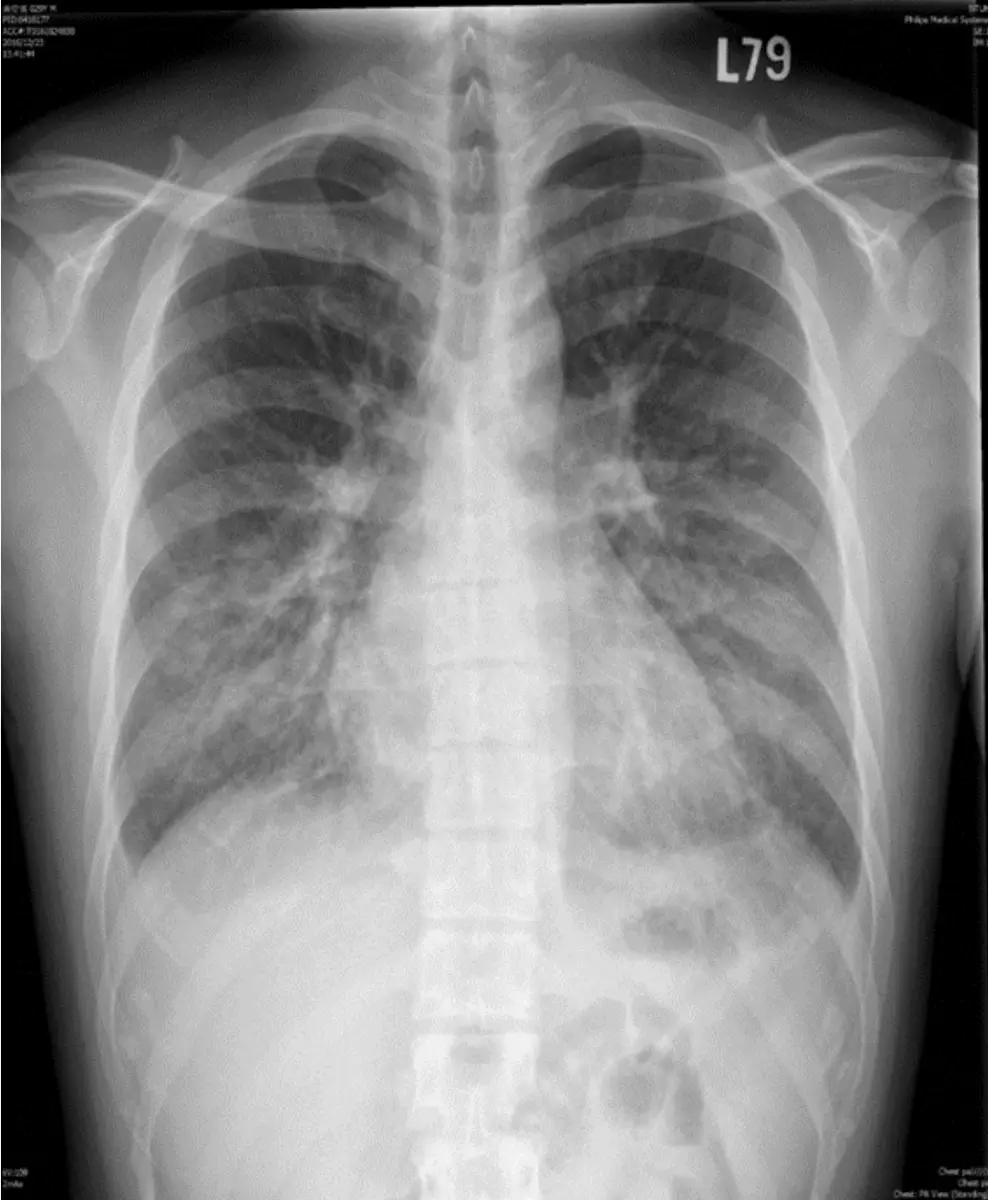

病人是位29歲男性電子工程師派駐中國深圳,三個星期來,時有間歇性發燒及逐漸性呼吸困難,先在深圳 門診求醫,初以為一般感冒治療,後以支氣管炎診斷治療罔效,乃急回台灣求醫。經檢查,意識: E4M6V5; BP: 122/75 mmHg; PR: 116/min; RR: 21/min; Temperature: 37.6℃; SpO₂: 94%(room air) 頸靜脈不怒張,未有貧血,胸部呈現瀰漫性濁音,心臟擴大,有Grade III/VI Diastolic murmurs at left upper sternal border,無肝脾腫大,無腹水。皮膚未有紅腫或出血斑點。2016/12/23心電圖及胸部X光如 圖。其血液、尿液及生化如次:Hemograms: WBC, 13.54(k/uL); RBC, 4.74(M/uL); Hb, 13.0 (gm%); HCT, 40.2(%); MCV, 84.8 (fL); MCH,27.4(pg); Platelet,329 (k/uL); Seg, 81.5(%); Eos, 0.2(%)。尿檢: 正常。請 問這位年青病人的最可能診斷是:

胸部X光:

• 心臟影明顯增大,心胸比>0.5;

• 肺門區血管影增粗,上肺野可見血管走勢增多(cephalization),提示肺靜脈壓升高;

• 周邊散在細碎浸潤影,伴有間質性改變(Kerley B lines、peribronchial cuffing)